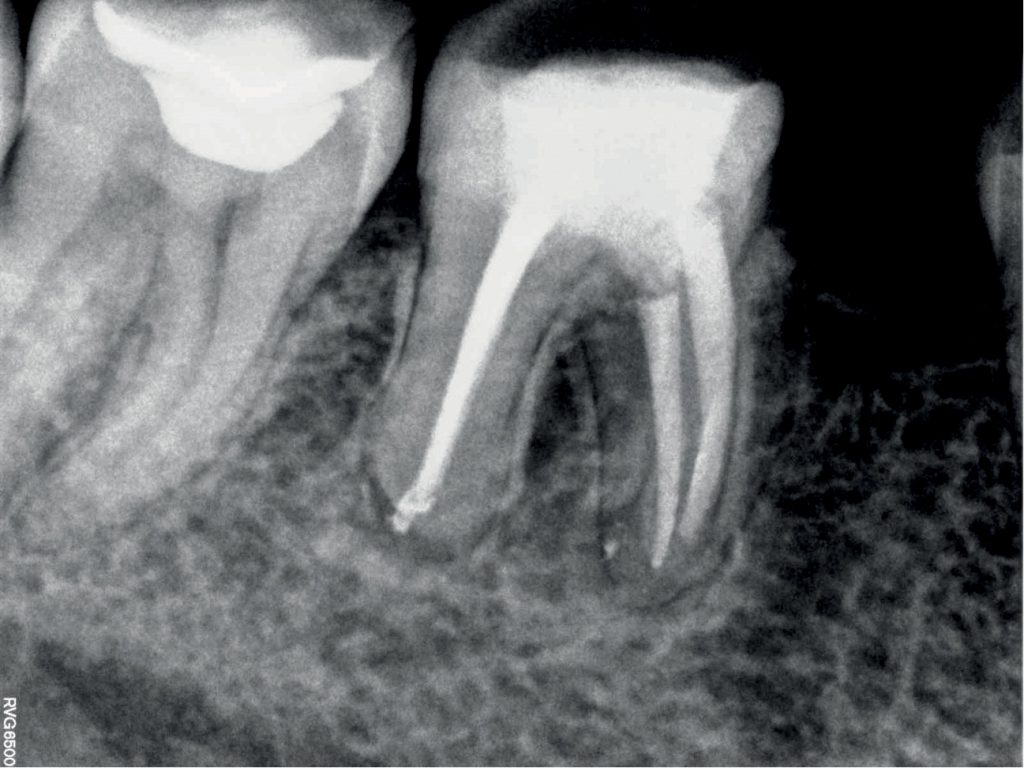

Monitorowanie wyników leczenia przewlekłych zmian okołowierzchołkowych u pacjentów chorych na cukrzycę różni się od klasycznego schematu.

Należy pamiętać, że w wywiadzie przeprowadzanym przed rozpoczęciem leczenia należy uzyskać informacje dotyczące chorób ogólnych, na które cierpi pacjent, w tym również cukrzycy. Informacje te mają duże znaczenie w zaplanowaniu właściwego leczenia, określeniu odpowiedniego czasu obserwacji oraz prawidłowej interpretacji wyników terapii. Pomyślność leczenia zmian okołowierzchołkowych zależy od początkowej ich wielkości i, co bardzo ważne, od ogólnego stanu zdrowia oraz funkcji układu immunologicznego.